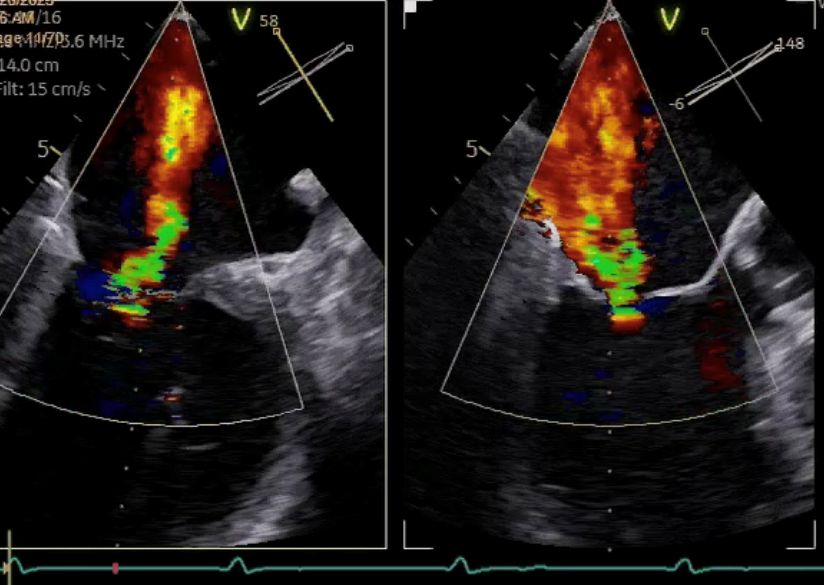

Vorher

Nachher

Die Echokardiographie ist ein zentrales diagnostisches Verfahren in der Beurteilung und Therapie von Herzklappenerkrankungen. Sie ermöglicht eine detaillierte Darstellung der Herzklappen, ihrer Bewegungen und des Blutflusses durch das Herz. Durch die Anwendung von Ultraschallwellen können Ärzte strukturelle Veränderungen, wie Verengungen (Stenosen) oder Undichtigkeiten (Insuffizienzen) der Klappen, präzise erkennen. Zudem erlaubt die Echokardiographie die Beurteilung der Herzfunktion und -größe, was für die Planung und Überwachung therapeutischer Maßnahmen essenziell ist. Insgesamt ist sie unverzichtbar für die Diagnose, Entscheidungsfindung und Nachsorge bei Herzklappenerkrankungen.

Die transösophageale Echokardiographie (TEE) liefert durch den Zugang über die Speiseröhre detailliertere Bilder der Herzklappen und angrenzenden Strukturen. Sie wird vor allem eingesetzt, wenn die TTE keine ausreichenden Ergebnisse liefert oder bei komplexen Fragestellungen wie Endokarditis-Diagnostik, Klappenprothesendysfunktion oder der Planung von Klappeneingriffen (z. B. M-TEER oder T-TEER). Die TEE ist invasiver und erfordert eine Sedierung, ermöglicht aber eine besonders präzise Beurteilung von kleineren Klappenfehlern und thrombotischen Veränderungen.